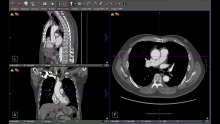

Screen Layout and Orientation

The video starts by introducing the layout of the screen. The top left displayed the sagittal slice, while the bottom left showed the coronal slice. The right side presented the axial slice. These anatomical slices were positioned in orthogonal planes, meaning they were positioned at 90-degree angles to each other. Once the planes were manipulated, they no longer represented true sagittal, coronal, or axial slices; however, for convenience, these terms were continued to be used. The bone window was employed for this demonstration, but other window settings may be more helpful depending on individual preferences or the specifics of the scan.